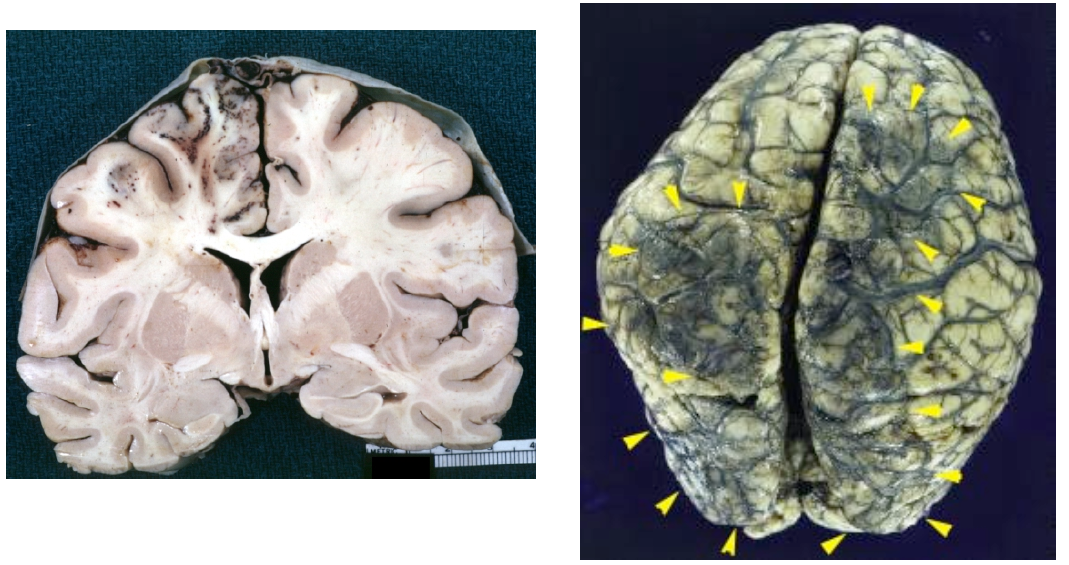

17 year old out parting at Elich’s and then got gastro and is overweight on OCPs. Presents with seizure then rapid decline.

Wa happened?

Venous Sinus Thrombosis

• Venous congestion over the convexities with parietal petechial hemorrhages.

Associated with:

– Post-partum

– Dehydration

– Hypercoagulable states

– Adjacent inflammation

(e.g., mastoiditis).